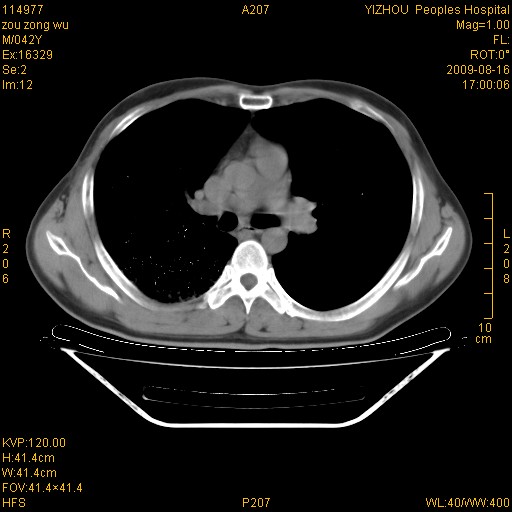

以下是引用zjzjr在2009-8-17 10:42:00的发言:[br]右侧间质性肺炎伴纤维化,右肺下叶肺囊肿伴感染(不除外外伤后引起),右肺野及胸壁软组织\\肝内见多发斑点状,中枪了吧.右侧胸膜肥厚\\粘连.